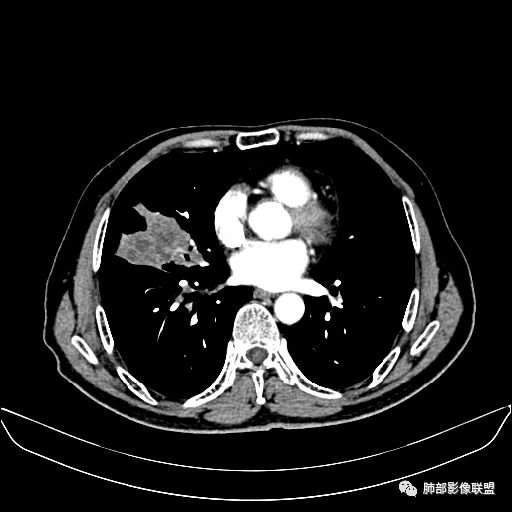

入院CT

老年男性,因“咳嗽咳痰1月余。”入院。病程中咳嗽咳痰,咳黄白痰,间断咯少许鲜红色痰血。PPD阳性。胸CT:右肺中叶外侧段支气管管腔阻塞,大片实性病变,病灶边缘光滑,部分边缘膨隆,可见分叶,肺门及纵隔可见肿大淋巴结,并可见钙化。增强可见病灶明显强化,而且延迟强化明显,病灶内多发低密度区,内见血管影,血管变细、部分血管破坏。考虑恶性病变可能性大,鉴别慢性肉芽肿性病变。

右肺中叶外侧段管腔阻塞、实性病变,病灶边缘光滑,可见分叶,肺门及纵隔可见肿大淋巴结,并可见钙化。增强可见病灶内多发低密度区。

胸CT:跨叶大肿块,主体在中叶,右中叶外侧段支气管阻塞,病灶部分边缘膨隆,可见分叶,部分边缘平直,肺门及纵隔可见肿大淋巴结。增强病灶不均匀强化,延迟强化明显,病灶内多发低密度区,内见血管飘浮,部分血管变细、模糊。考虑:恶性病变可能性大,大细胞?淋巴瘤?鉴别慢性肉芽肿性病变。

右肺中叶软组织肿块,外围向内生长,叶间胸膜向前内移位,肿块近肺门侧跨叶,中叶外侧段支气管截断,密度不均匀,双侧肺门及隆突下见肿大淋巴结,增强后呈中度不均质强化,肺动脉供血,多发坏死区,边界尚清,坏死区域内见结构,结合病史考虑恶性,鉴别诊断1结核,爬行征是沿支气管树分布,外宽,内窄,周围有卫星灶,内气管狭窄后扩张,此例沿叶间胸膜长轴分布,气管有截断,不典型。2炎性肉芽肿,符合的地方下方层面增强后延迟性轻度环形强化,不符临床无发热等急性感染病史,实验室指标不符,病灶周围渗出及慢性炎性改变有,不明显。